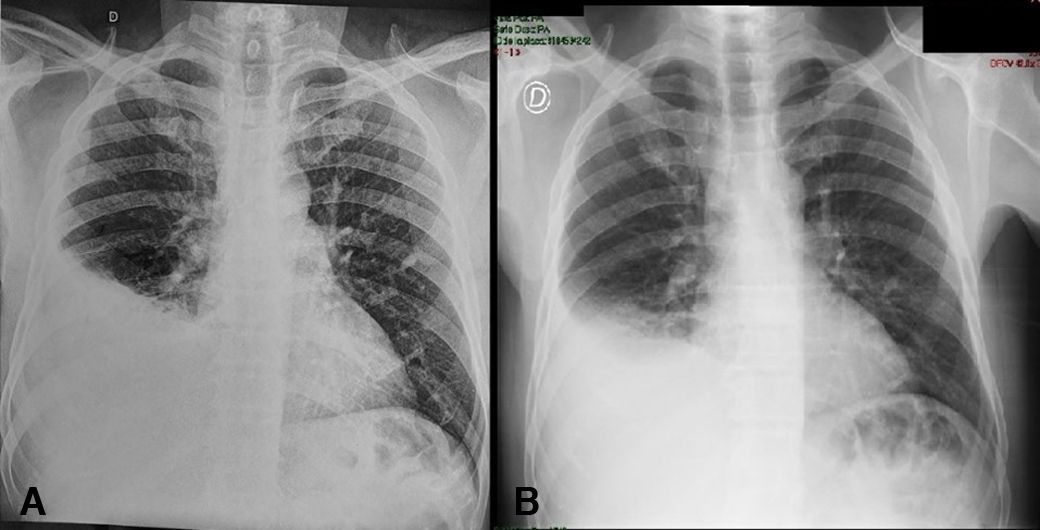

Paciente de género masculino y 48 años de edad. Nació y vive en la ciudad de Buenos Aires, Argentina, trabaja en la construcción y refiere no haber realizado viajes, ni dentro ni fuera del país. Como antecedentes patológicos expone que fue fumador de 15 cigarrillos al día entre los 15 y los 40 años de edad. Dos días antes de la consulta comenzó con fiebre, tos no productiva y dolor en hemitórax derecho. Con estos síntomas se presentó en el servicio de guardia de un hospital general de agudos. Allí le realizaron una radiografía frontal simple de tórax (fig. 1A) y le prescribieron amoxicilina con ácido clavulánico (1g/12h). Seis días más tarde volvió a consultar por continuar la fiebre, esta vez al servicio de guardia del Hospital de Infecciosas FJ Muñiz, donde se le solicitó una nueva radiografía (fig. 1B), se le realizó una punción pleural para llevar a cabo un examen fisicoquímico y bacteriológico. Tras dicho procedimiento el enfermo continuó con el mismo tratamiento antibiótico en su domicilio, con la indicación de realizar reposo y consultar nuevamente en el caso de experimentar falta de aire o tener fiebre que no cediera con antipiréticos. Cinco días más tarde el enfermo volvió al servicio de guardia refiriendo astenia, adinamia, pérdida de peso y equivalentes febriles en días alternos.

La criptococosis pulmonar puede presentar distintos patrones radiológicos. En enfermos con el VIH suele observarse intersticiopatía y/o nódulos pulmonares uni o bilaterales11. En los enfermos inmunocompetentes que padecen criptococosis pulmonar por Cryptococcus gattii suelen aparecer consolidaciones o masas que, frecuentemente, generan la sospecha de neoplasia pulmonar15. El derrame pleural es poco frecuente en esta enfermedad6, pero cuando se presenta se suele observar en personas inmunocomprometidas, aunque también ha sido descrito en algunos casos de enfermos inmunocompetentes17. Cuando especies de Cryptococcus son aisladas de un material estéril como es el líquido pleural deben considerarse patógenos primarios, siempre y cuando se identifique el complejo Cryptococcus neoformans/Cryptococcus gattii.